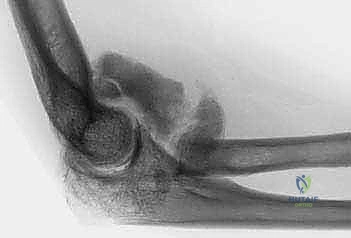

- الأشعة السينية (X-rays): لتقييم شكل العظام، البحث عن الكسور القديمة، وتحديد أماكن النتوءات العظمية والأجسام الحرة الكبيرة.

- الأشعة المقطعية ثلاثية الأبعاد (3D CT Scan): وهي الأهم قبل الجراحة. تعطي الجراح خريطة مجسمة دقيقة لكل نتوء عظمي وكل حاجز ميكانيكي داخل المفصل، مما يسهل استهدافه بالمنظار.

وهو السبب الأكثر شيوعاً. أي كسر حول المرفق (مثل كسور عظمة العضد السفلية، كسور رأس الكعبرة، أو كسور الزج) يمكن أن يؤدي إلى تيبس شديد. يحدث هذا بسبب:

* النزيف داخل المفصل (Hemarthrosis) الذي يتحول إلى نسيج ندبي.

* التعظم غير الطبيعي (Heterotopic Ossification) حيث يتكون عظم جديد داخل الأنسجة الرخوة.